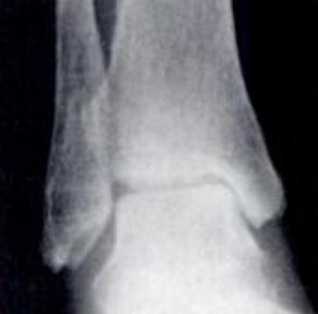

Классификация артроза голеностопного сустава.

Субхондральный склероз и начало роста остеофитов

Сужение суставной щели в медиальной области

Дальнейшее сужение суставной щели в медиальной части сустава до контакта субхондральной кости

Сужение суставной щели в области крыши купола таранной кости до контакта субхондральной кости

Полная облитерация сустава

Для диагностие выполняются рентгенограммы в прямой, боковой и косых проекциях, с нагрузкой весом тела. На рентгенограммах определяется сужение суставного пространства, субхондральный склероз, формирование кист, деформация, рост остеофитов.